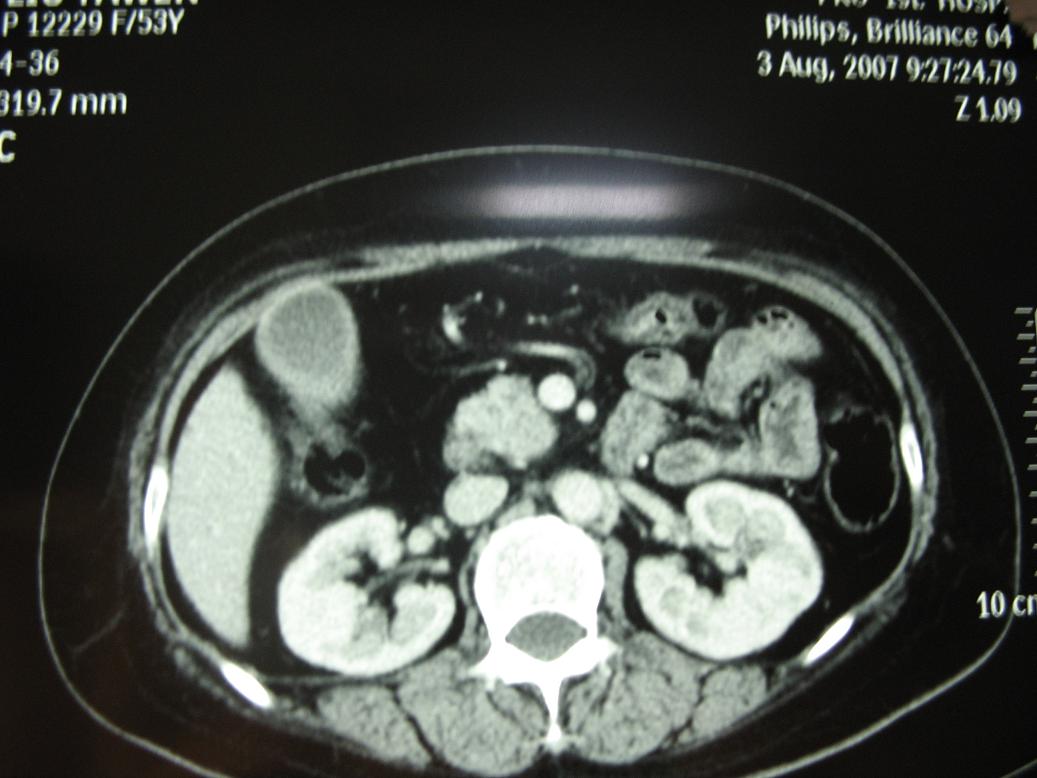

标题: CT17151:女 53岁 腹痛数月余 轻微黄疸 [打印本页]

女 53岁 腹痛数月余 轻微黄疸

1)考虑胰头癌。2)胆囊炎。

壶腹周围占位(钩突ca?)

胰腺钩突mt

支持胰腺钩突ca伴胆系梗阻,胆囊炎

考虑 胰头癌可能性大。